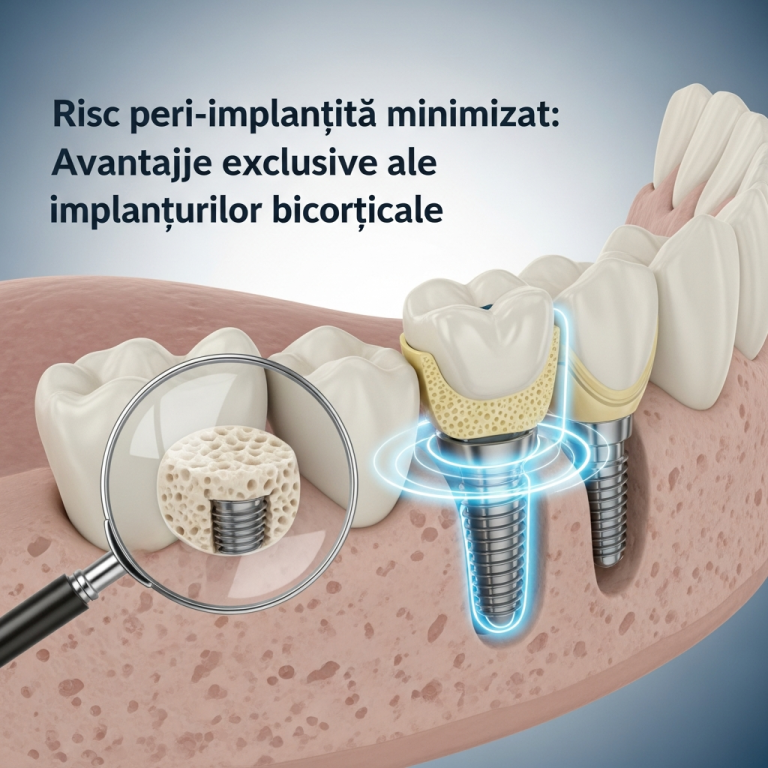

Menținerea sănătății gingiilor este fundamentală pentru succesul pe termen lung al implantelor dentare. Inflamația gingivală, sau periimplantita, reprezintă o complicație majoră care poate compromite stabilitatea osului și a implantului. Conform studiilor recente (2025–2026), prevenția eficientă se bazează pe o strategie multifactorială care începe încă din faza de planificare. Acest gid sintetizează protocoalele actuale de igienă și urmărire medicală, esențiale pentru a minimiza riscul inflamator și a asigura integritatea implantului.

Controlul factorilor de risc sistemici și locali reduce dramatic incidența periimplantitei. Cercetările actuale evidențiază:

- Managementul bolilor sistemice: un control riguros al diabetului sau al osteoporozei.

- Corectarea încărcării ocluzale: pentru a evita suprasolicitarea implantului.